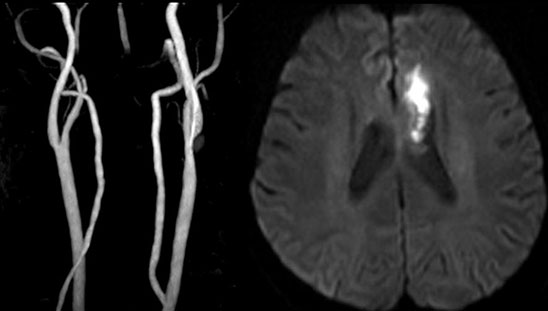

MAGNETOM Spectra 3.0T新一代聚能光谱磁共振

MAGNETOM Spectra 3.0T聚能光谱磁共振